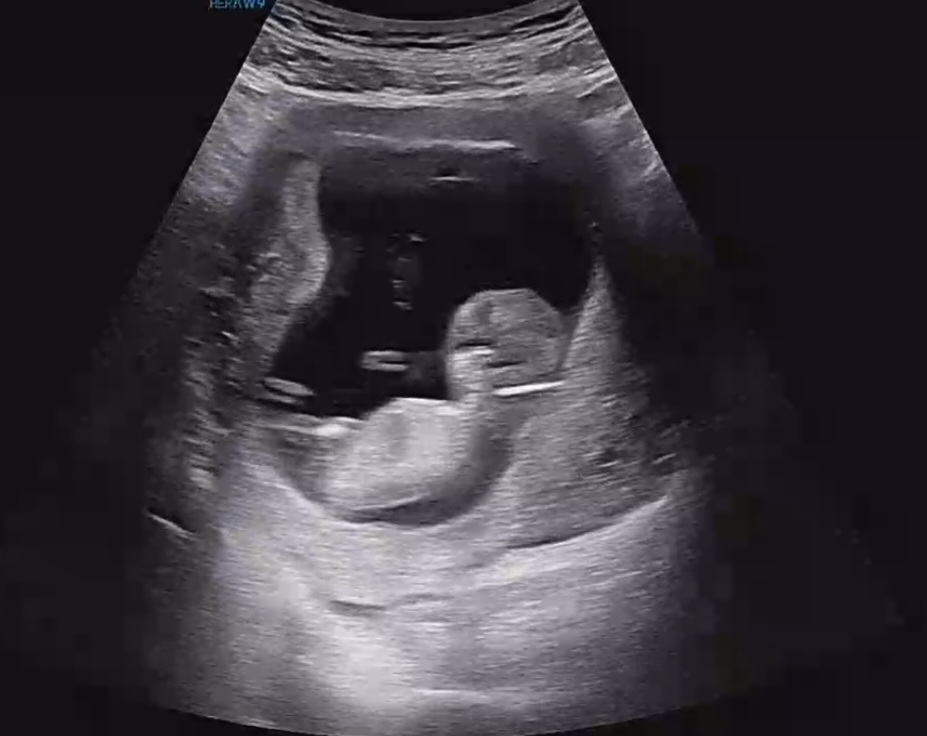

11주 4일차 각도법 봐주세요~~~

오늘 1차 기형아 검사하고 왔는데 아직 티는 안나는거 같은데 각도법 한번 봐주세요~~